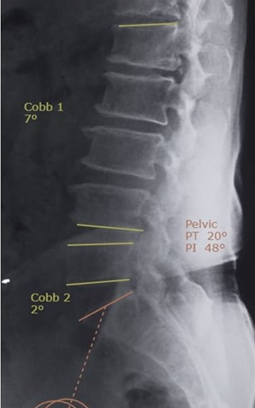

Do Spino-pelvic Parameters Predict Development of Spondylolisthesis in Degenerative Disc Disease at the L4-5 Level

K V Menon , Naveen Tahasildar , Mantu Jain , S Sathish Kumar